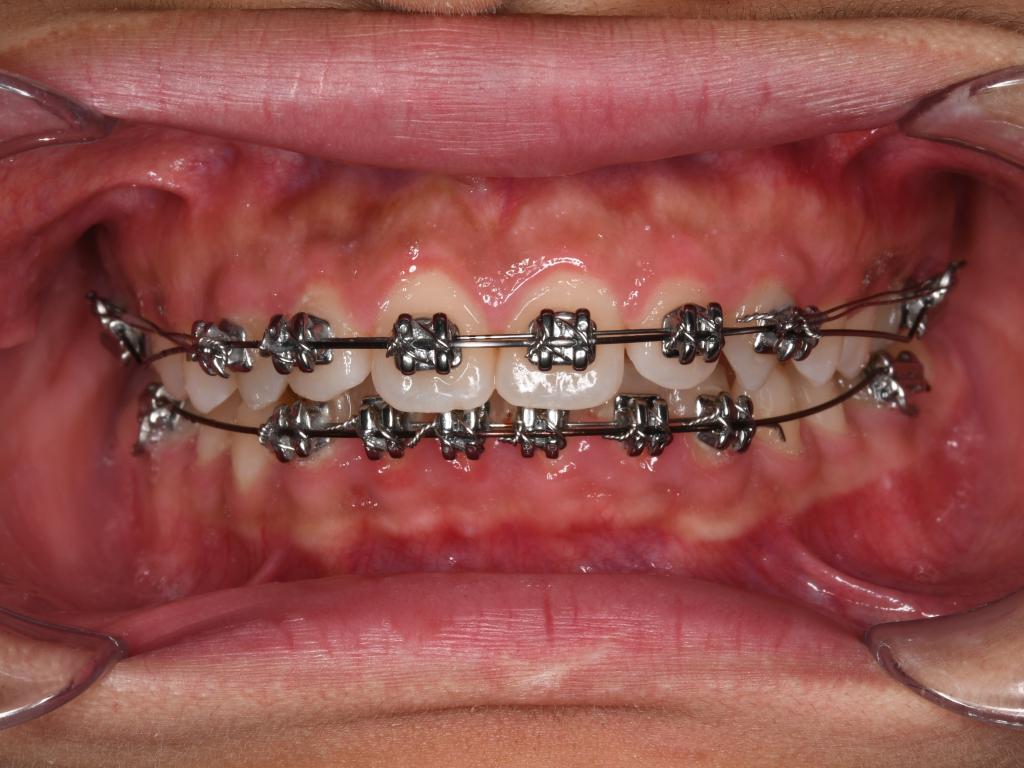

(2) 做好口腔清洁,保持牙齿与矫治器的清洁卫生。

(3) 进食时注意避免啃咬坚硬食物,减少矫治器损坏与脱落。

(4) 因为疫情短期无法复诊:为了大家的安全考虑,可延期就诊,偶尔的复诊延期,不会影响矫治效果。必要时与主治医生取得联系,拍摄口内照片图文咨询。